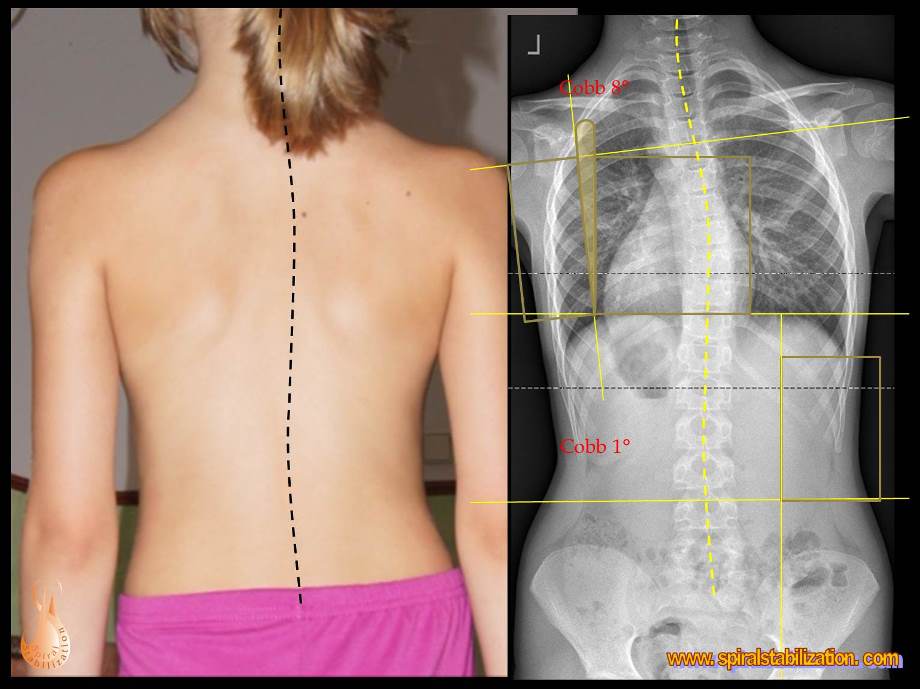

3 - Scoliosi

2 - Scoliosi fino ai 6 anni

Scoliosi fino ai 6 anni

B - 3 - 2